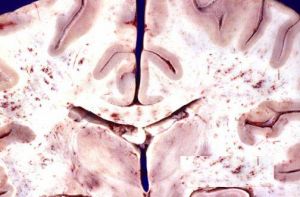

外傷後腦脂肪栓塞病理圖發病機制:

外傷後腦脂肪栓塞及急性肺水腫。進入腦血管的脂肪栓子常使腦內多數小血管栓塞,在大腦白質及小腦半球造成廣泛的點狀瘀斑和出血性梗死灶,腦水腫反應亦較一般為重,故病人常有病情加重或有新的神經功能損害對創傷後脂肪栓塞綜合徵的主要病變究竟是在腦還是在肺尚有分歧。Sevitt認為主要病變在腦強調組織病變的產生與脂肪栓子的大小數量、引起缺氧的時間小血管有無側支以及器官對缺氧的敏感程度等等均有密切關係。腦組織對缺血、缺氧敏感而且耐受性極差,容易引起損害。臨床上以神經系統損害為主又先於肺部症狀的病例時有發現腦栓塞是導致死亡的主要原因。Peltier則認為主要病變在肺部,強調脂肪栓塞的原發病變在肺由於肺脂肪栓塞之後所造成的呼吸功能不全及低血氧症是使腦組織產生繼發性缺氧的主要原因,這種腦缺氧屬缺氧性缺氧而不是缺血性缺氧。由此看來孰輕孰重則需看何者病理改變更為嚴重,故每個病人不盡相同。